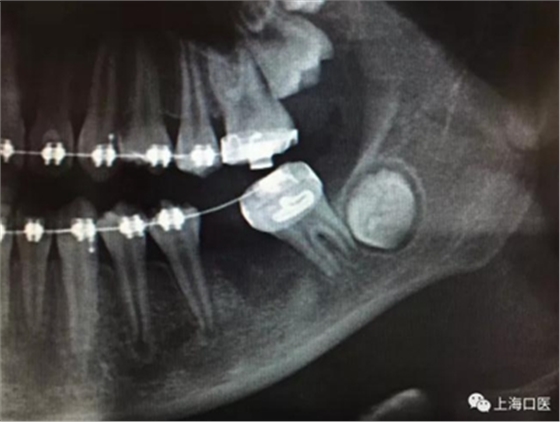

這是上海武廣增正畸工作室接診的一例非常規(guī)拔牙矯治病例,患者女性,初診年齡14歲。LL6殘冠拔除。LL7近中平移取代LL6,我們上傳了該患者一組下頜磨牙近中平移連續(xù)矯治過程的正畸X線片,與正畸界朋友分享。